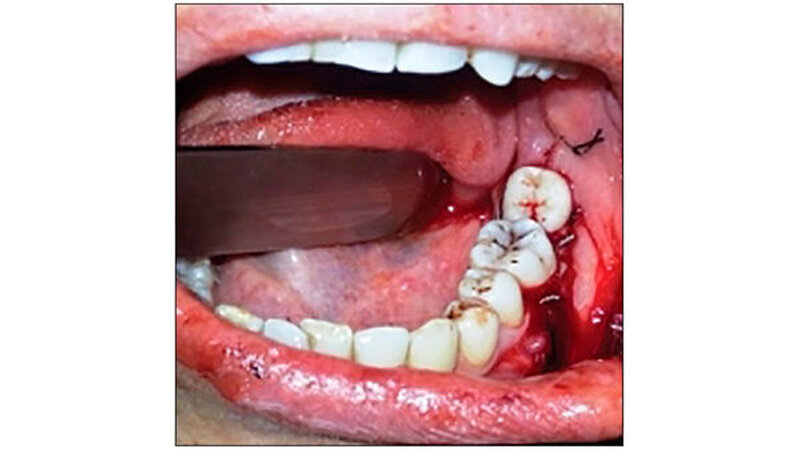

Die Anästhesie erfolgte mit Lidocain-Hydrochlorid (Lignox zwei Prozent, Indoco-Remedies Ltd., India). Zuerst erfolgte die Extraktion von Zahn 37 extrahiert - ohne die Corticales zu beschädigen. Danach erst erfolgte die Extraktion von Zahn 38, um hier die Gewebeschäden so gering wie möglich zu halten. Eine horizontale intrakrevikuläre Inzision wurde durchgeführt. Zahn 38 wurde bis zur Transplantation in isotoner Kochsalzlösung gelagert, parallel eine Socket Preparation vorbereitet (Abbildung 2).

Zahn 38 wurde in das vorbereitete "Bett" von 37 transplantiert. Mit Nahtmaterial (Nähte India Pvt Ltd, Indien) stabilisierten die Zahnärzte die Position des transplantierten Zahns (Abbildung 3). Die intraradikuläre Schienung erfolgte mit formbarem kieferorthopädischem Draht (Tru-Bogen, Ormco Ltd., USA). Anhand eines postoperativen Röntgenbilds wurde die neue Position des 38 überprüft. Zur Unterstützung des Heilungsprozesses bekam die Patientin einen parodontalen Wundverband (Coe-Pack, G C Indien) angelegt.